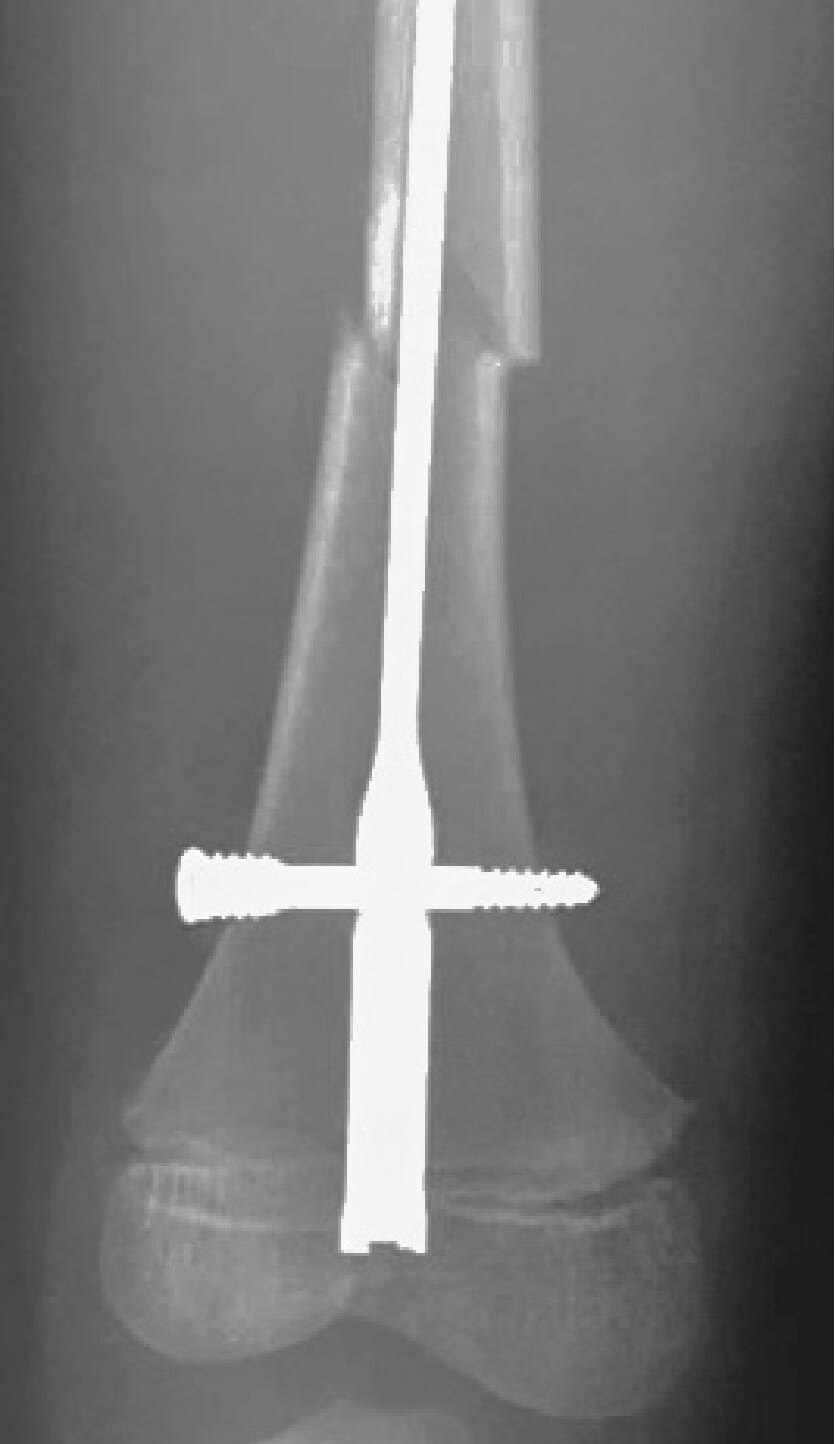

Ortho fracture repair figure 1AFigure 1A: This 11-year-old boy was treated in Mongolia with a retrograde femoral nailing for his distal femoral shaft fracture.

Ortho fracture 1BFigure 1B: Nine months later, radiographs demonstrate appropriate growth of the distal femoral with change in position of the nail versus the growth plate and a bony line called a Harris growth arrest line, which supports that the bone is growing reasonably.